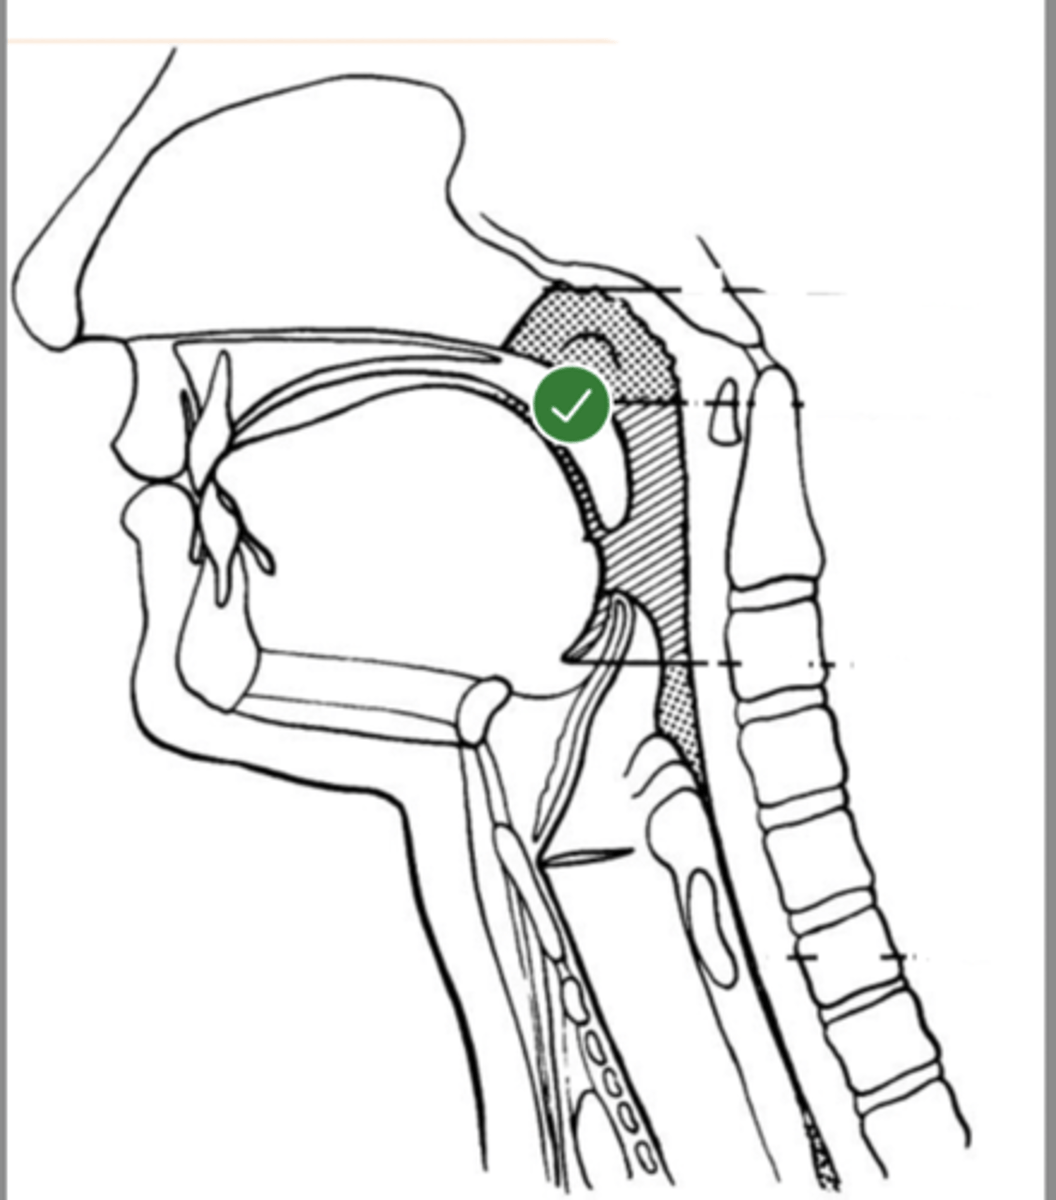

Label Nasopharynx (lateral view)

Label Nasal cavity (lateral view)

Label oropharynx (lateral view)

Label hypopharynx/ hylolarynx

Label tongue (lateral view)

Label soft velum/ palate (lateral view)

Label hard palate (lateral view)

Label mandible (lateral view)

Label base of tongue (lateral view)

label hyoid bone (lateral view)

Label epiglottis (lateral view)

label Line of true vocal folds (lateral view)

label Thyroid cartilage (anteriorly) (lateral view)

Label posterior cricoid (lateral view)

Label esophagus (lateral view)

label anterior tongue (lateral view)

Label posterior/ back of tongue (lateral view)

Label velum/ soft palate (lateral view)

Label thyroid cartilage (lateral view)

Label trachea (lateral view)

Label upper esophageal sphincter (lateral view)

Label posterior pharyngeal wall (lateral view)